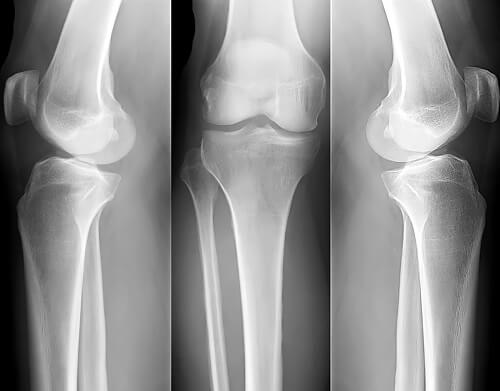

Remedios caseros para la osteoporosis